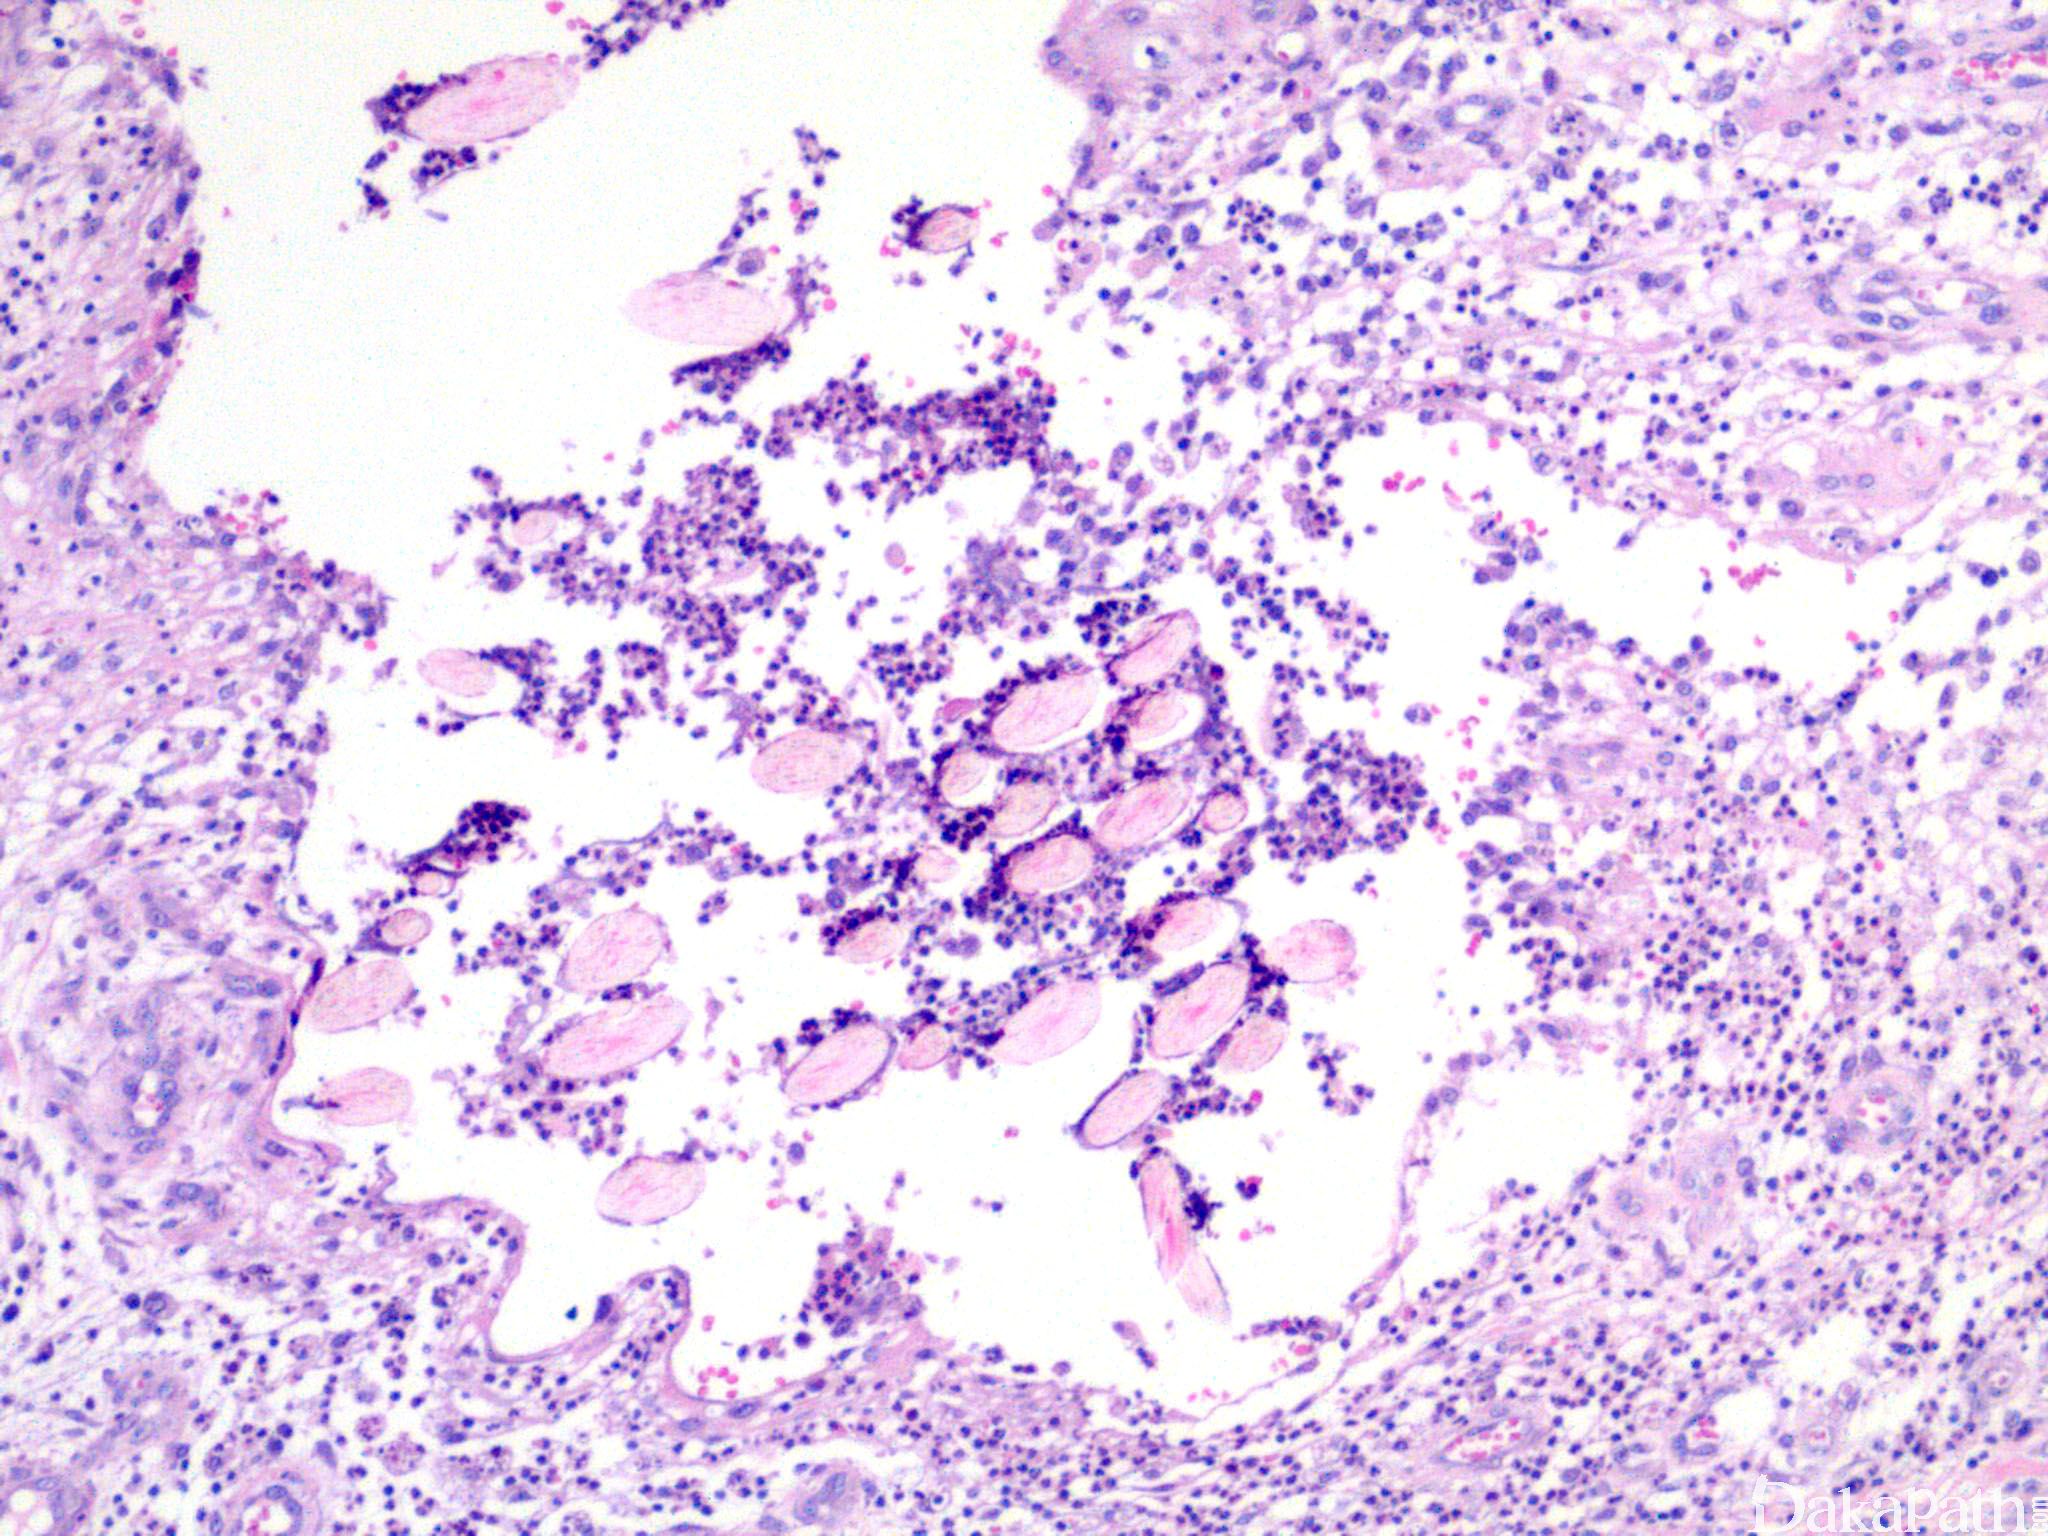

pilonidal cyst